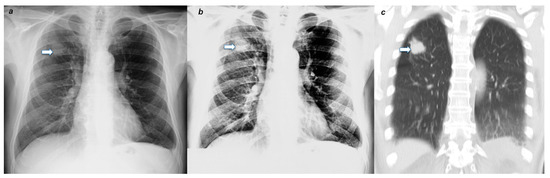

3. Description and Performance Evaluation of the Algorithm

4.2. Radiological Evaluation and Statistics